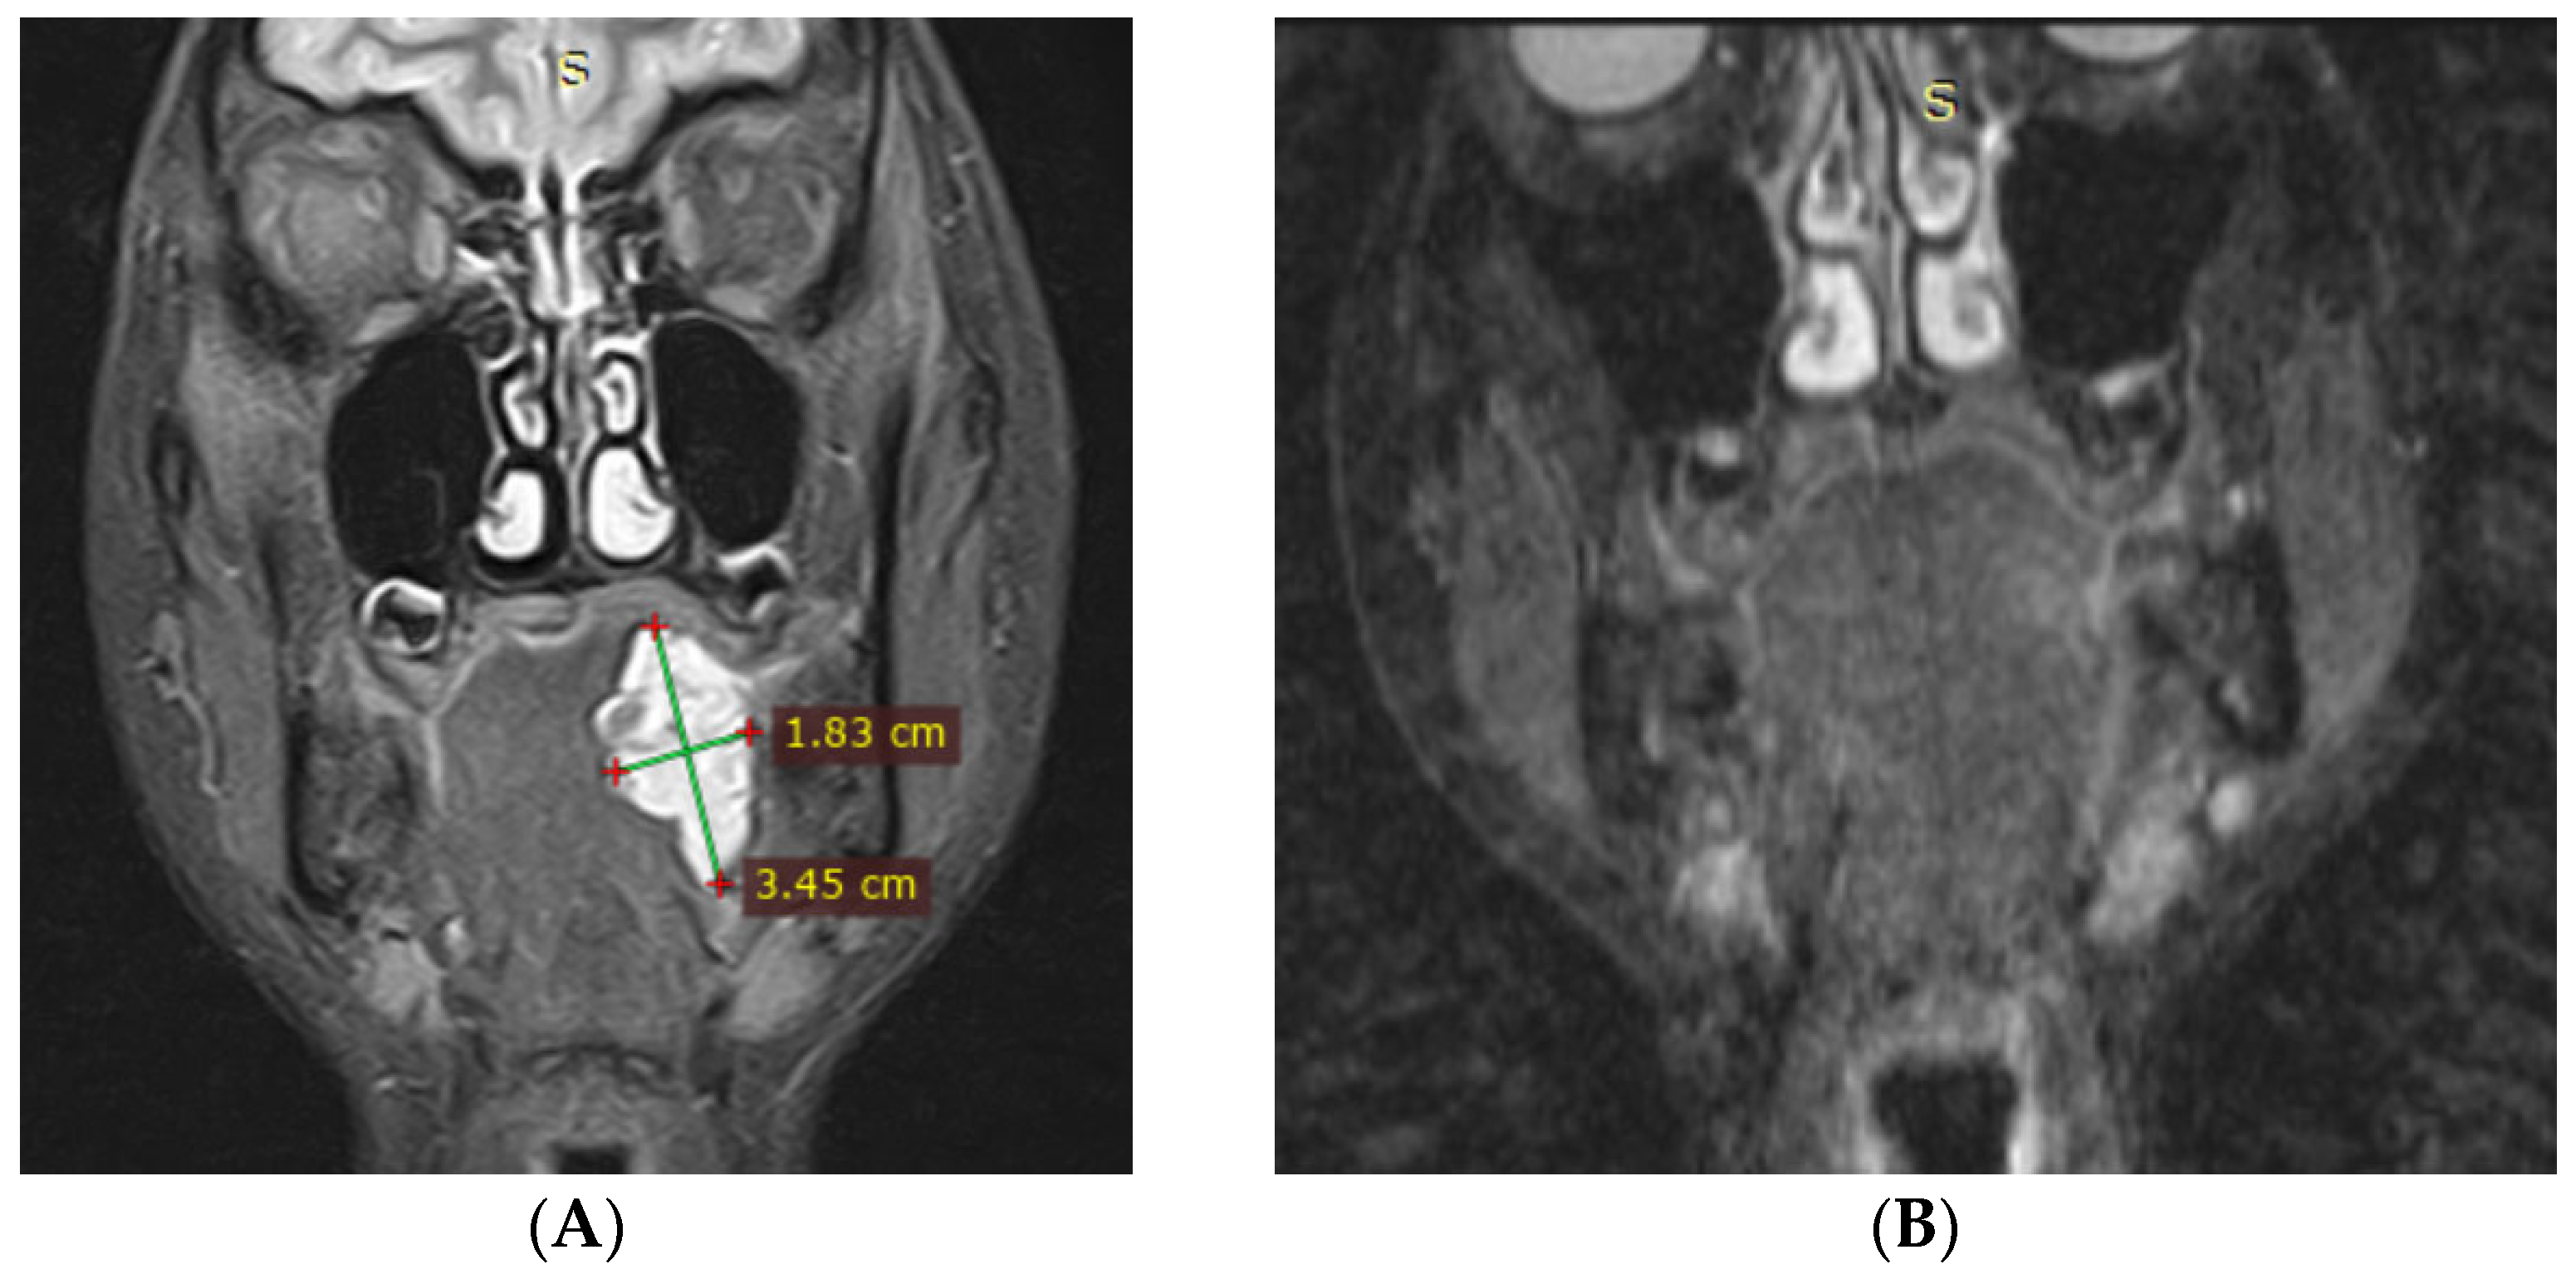

3.1. Magnetic Resonance Imaging (MRI) Findings

| 12 | F | 14 | Total tongue involvement | 12 | 10,192 | 4090 | Significant reduction (>50%) | None |